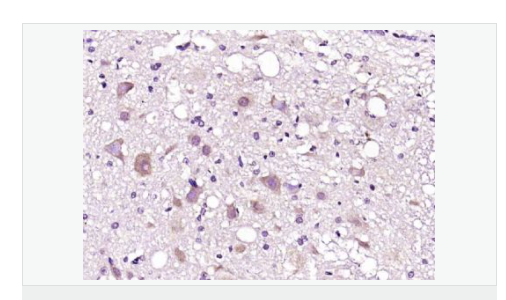

| 產(chǎn)品應(yīng)用 | WB=1:500-2000 ELISA=1:5000-10000 IHC-P=1:100-500 IHC-F=1:100-500 IF=1:50-200 (石蠟切片需做抗原修復(fù)) not yet tested in other applications. optimal dilutions/concentrations should be determined by the end user. |